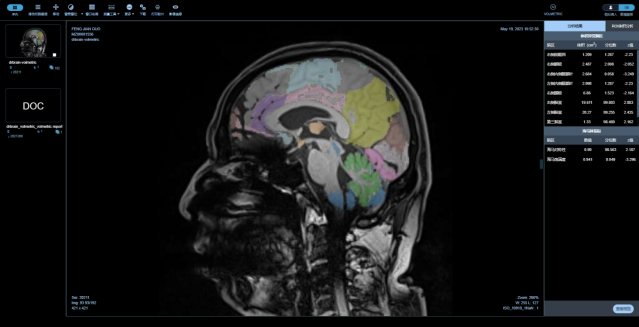

中樞神經(jīng)系統(tǒng)核磁影像AI診斷分析平臺

是專注在中樞神經(jīng)系統(tǒng)疾病的人工智能診斷分析平臺,基于醫(yī)未自行搭建的全年齡段中國人群全腦結(jié)構(gòu)影像數(shù)據(jù)庫,結(jié)合前沿的大數(shù)據(jù)分析和人工智能等核心技術(shù),快速、精準(zhǔn)評估全腦結(jié)構(gòu)變化、腦白質(zhì)病變、微出血灶及腦血流量等,以量化、直觀的結(jié)果,輔助臨床做出超早期的精準(zhǔn)診斷及疾病進(jìn)展預(yù)測。

最全面的分區(qū)

最全面的腦結(jié)構(gòu)分區(qū),快速獲取全腦100個精細(xì)腦區(qū)共165項指標(biāo),精度達(dá)到毫米級

量化、直觀的報告(部分)